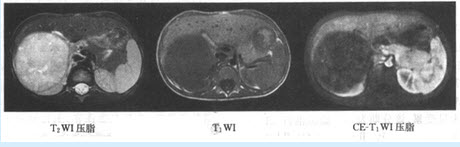

患者,男,63岁,重症肌无力1个月,胸部MRI平扫图像如下:

(单选题)最可能的诊断为()

(单选题)此病变的MR影像表现为()

A:T1WI高信号,T2WI低信号

B:T1WI高信号,T1WI高信号

C:T1WI低信号,F1T2WI低信号

D:T1WI低信号,F1T2WI高信号

E:T1WI低信号,T1WI低信号